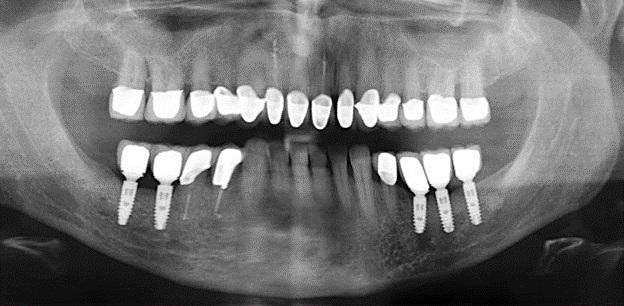

Fig. 1: Radiografia panoramica della situazione iniziale nel Panoramic radiograph of initial situation in 2004.

Fig. 1: Radiografia panoramica della situazione iniziale nel 2004.

Un paziente di 52 anni si è presentato nella nostra clinica per la prima volta nel 2004 a seguito della perdita dei denti nel terzo quadrante, esprimendo il desiderio di un nuovo restauro protesico. La diagnostica parodontale e radiologica ha rivelato la necessità di un ampio trattamento parodontologico. Inoltre, ai denti 48, 28 e 27 è stata attribuita una prognosi molto scarsa e sono stati successivamente estratti (Fig. 1). A seguito del trattamento periodontologico sistematico completato con successo, è stato inserito una protesi dentale fissa con l'inserimento di cinque impianti nelle regioni dentali 35, 36, 37, 46 e 47. Il trattamento protesico dei denti naturali è stato effettuato con corone rivestite in ceramica di biossido di zirconio; gli impianti two-piece composti da abutment singoli in biossido di zirconio e corone similmente rivestite in ceramica di biossido di zirconio (base Cercon colorata, Dentsply Sirona Lab). L'inserimento definitivo del restauro protesico è avvenuto nel 2005.